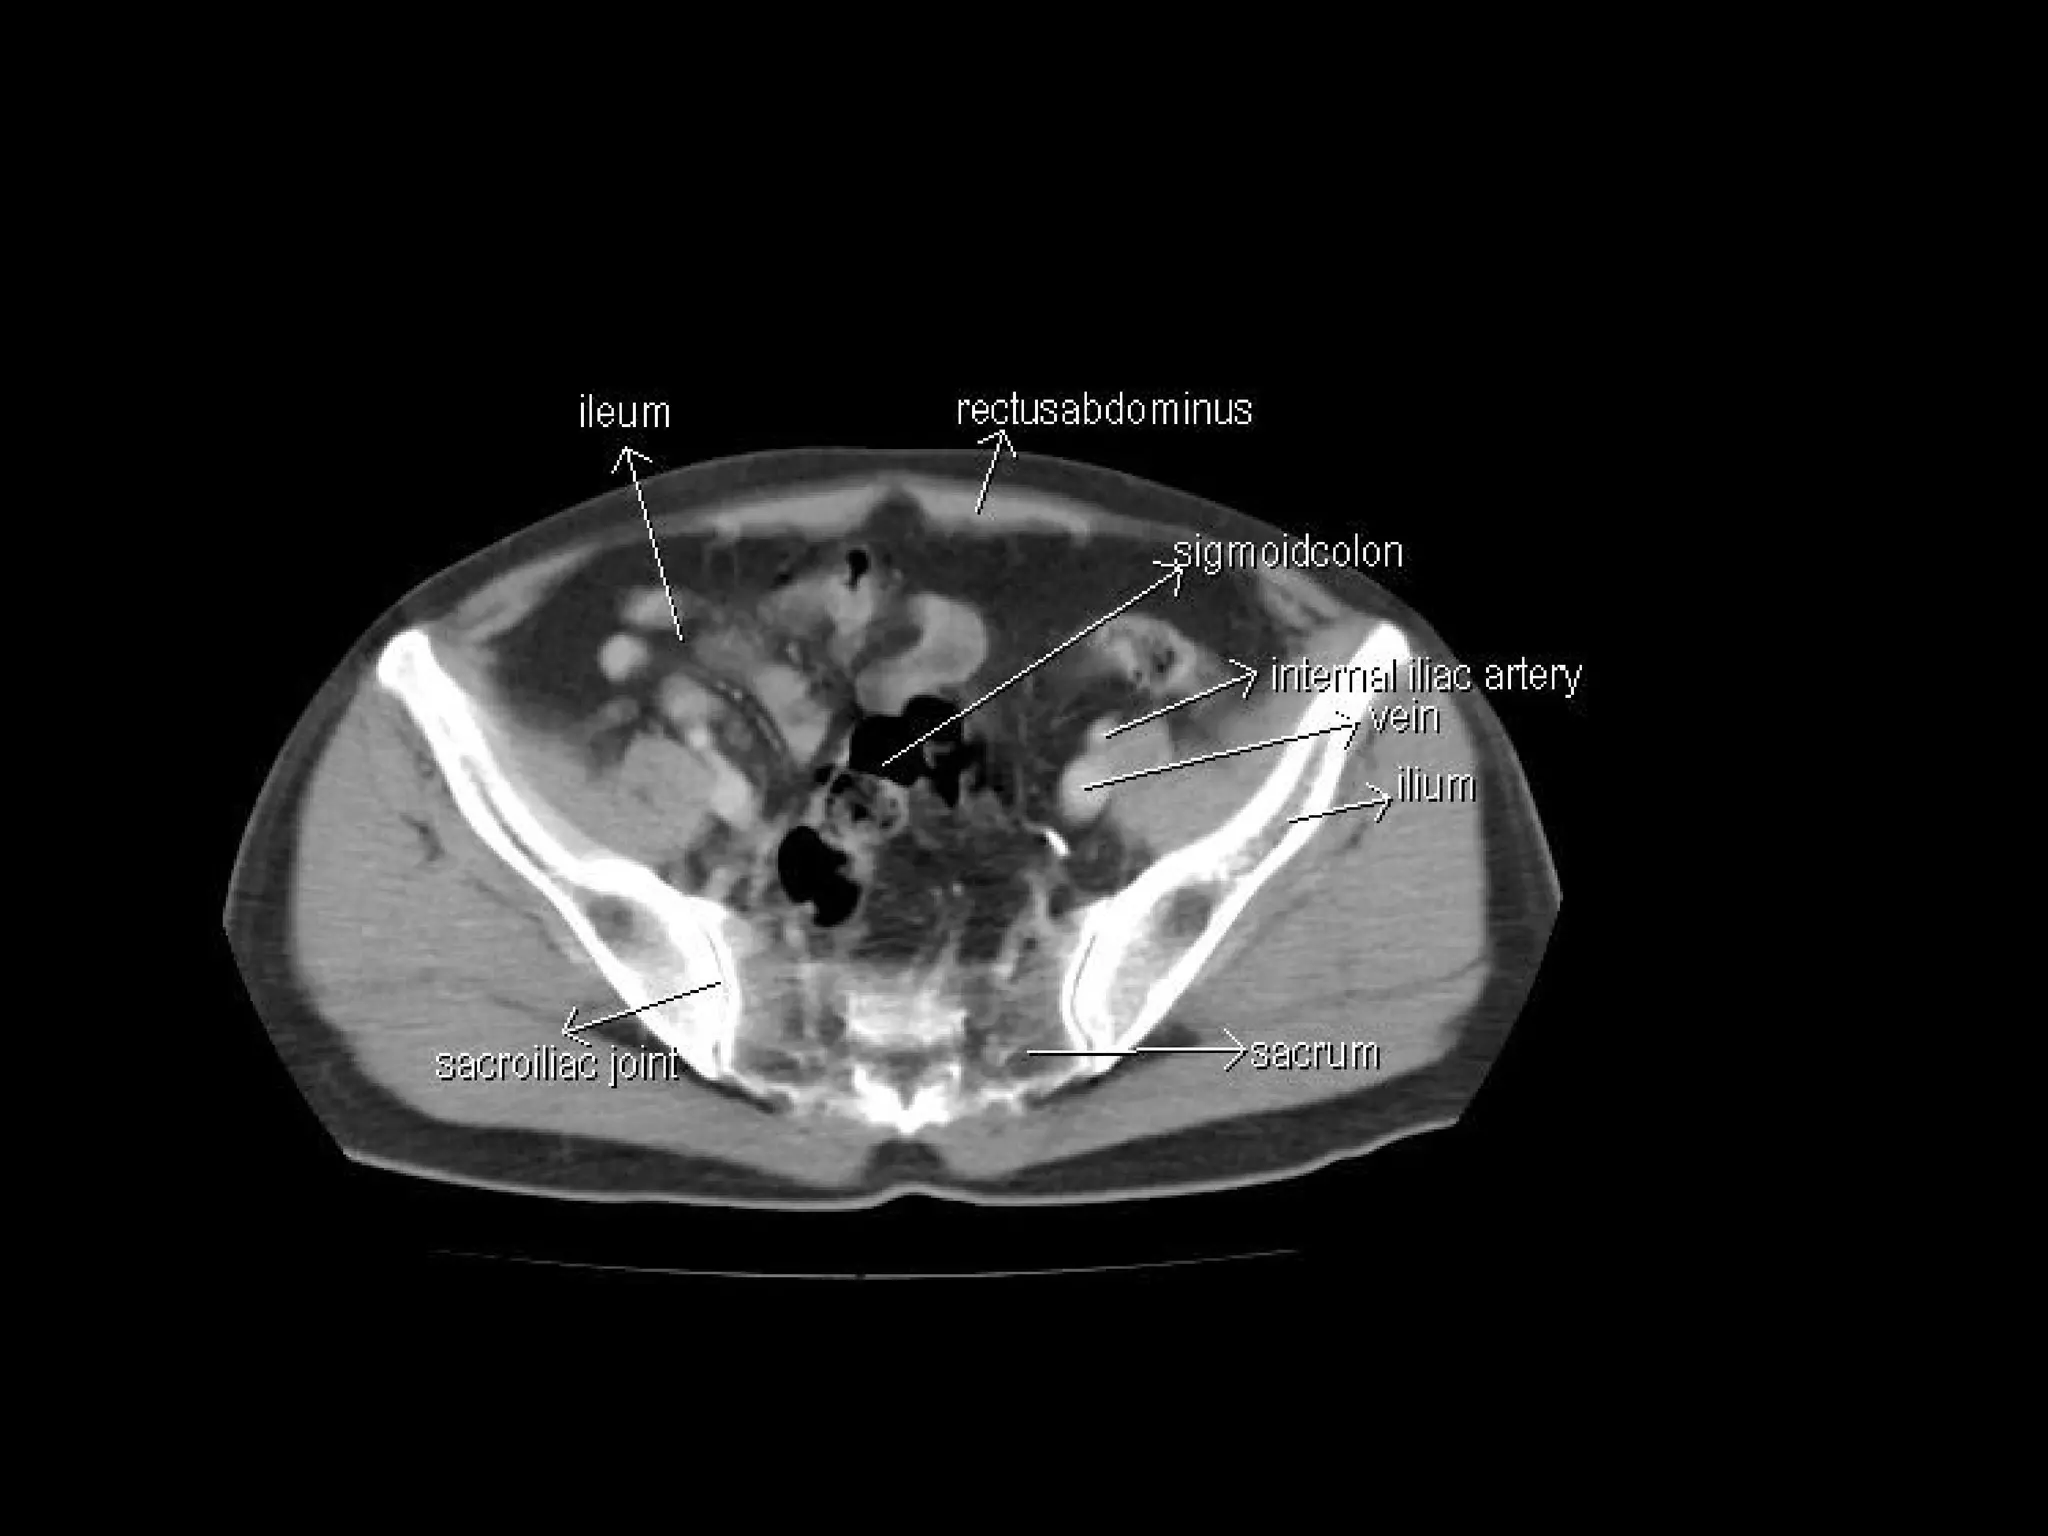

Radiographers are medical professionals who perform diagnostic imaging examinations and procedures to help physicians diagnose and treat diseases. They work under the supervision of radiologists to operate X-ray, CT, MRI, ultrasound and other medical imaging equipment and must have a strong understanding of human anatomy and pathology. Radiographers are responsible for correctly positioning patients, ensuring proper imaging techniques are used, and evaluating the quality of the resulting images.